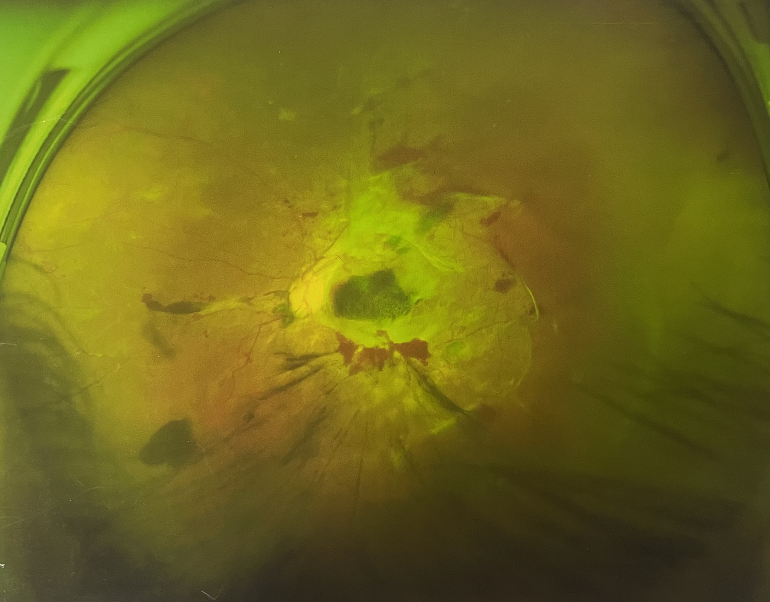

由于王女士的左眼沒(méi)有聽(tīng)從醫(yī)生盡快做手術(shù)的建議,一直耽誤,從4月前的0.4視力逐漸下降到僅剩眼前手動(dòng),導(dǎo)致左眼發(fā)展到糖尿病視網(wǎng)膜病變VI期(屬于6期糖網(wǎng)中的晚期),已經(jīng)產(chǎn)生大量新生血管+纖維增值+廣泛牽拉性視網(wǎng)膜脫離,由于耽誤了病情,且病情發(fā)展異常迅速,導(dǎo)致目前左眼連保住眼球都很困難。

“而如果4月余前,左眼及時(shí)手術(shù)(當(dāng)時(shí)左眼病情比右眼輕,增殖膜還未累及黃斑),左眼將恢復(fù)的比右眼還好,甚至可以恢復(fù)到0.8或1.0,而現(xiàn)在連保住眼球的機(jī)會(huì)都很渺茫”,張小虎醫(yī)生表示實(shí)在可惜。

4個(gè)月前的左眼

左眼發(fā)展到糖尿病視網(wǎng)膜病變VI期